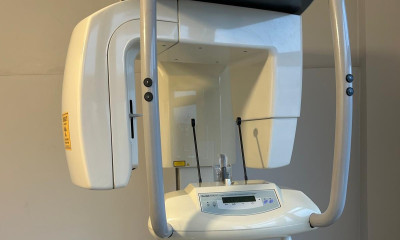

MYRAY HYPERİON X7 ASANSÖR KARTI DEĞİŞİMİ

Myray Hyperion X7 cihazındaki dikey hareket arızası nedeniyle asansör kontrol kartı yenisiyle değiştirilmiş ve cihaz çalışır hale getirilmişti